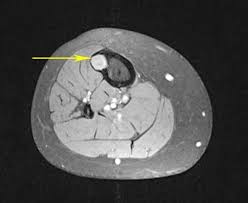

They show the different appearances of acc lung mets. Other names for this test: What is a ct scan with contrast? If not spread, you could conceivably see obstruction or changes in the bowel wall but it would likely be a big tumor nonetheless. I was then directed to lay down on the table.

Abdominal And Pelvic Ct from www.radiologyinfo.org The computer puts them together to make a 3 dimensional (3d) image. Early colorectal cancer can be subtle on ct scans showing only mild wall thickening, small polyps, or subtle lymph nodes in atypical draining location. Nothing found on us scan but fatty liver. I had my half way scan today so i'm now on. This shows the cancer more clearly. Acc has a tendency to spread to the lungs among other organs. Lab tests used to diagnose kidney cancer include: They show the different appearances of acc lung mets.